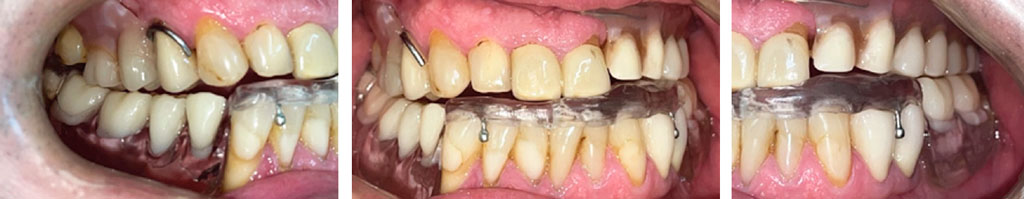

Рис. 2. Зубные ряды пациента в вынужденном положении нижней челюсти

Fig. 2. Patient’s teeth with a forced position of the mandible

Рис. 5. Зубные ряды пациента с каппой

Fig. 5. Patient’s teeth with the immobilizing splint